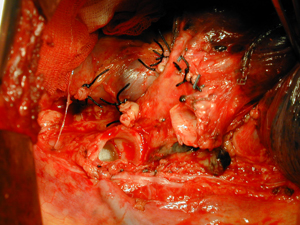

Εικόνα 4

Οπισθιοπρόσθια ακτινογραφία θώρακος μετά από δεξιά λοβεκτομή με βρογχοπλαστική πέντε χρόνια μετά από την επέμβαση για μη μικροκυτταρικό καρκίνο πνεύμονος. Πλήρης έκπτυξη του κάτω και μέσου λοβού.